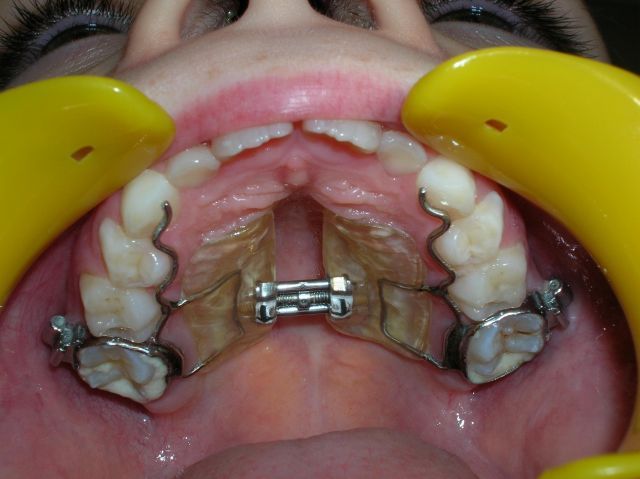

Disjoncteur

Sous ce charmant nom (!) se cache un appareil particulièrement efficace et discret (ne se voit pas de l'extérieur). Rapidement et sans douleur, il permet d'élargir les maxillaires trop étroits.